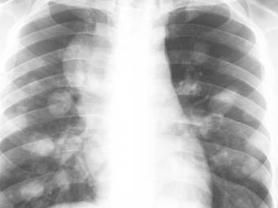

轉移性肺癌的X線表現:

(1)結節型 通常是肺小動脈和靜脈內的小癌栓所致。X線線上表現為單個、數個或數十個肺部結節,結節病灶分布在下肺葉較上肺葉多。部分轉移性肺癌病灶表現為粟粒型。單發轉移性肺癌胸部CT表現為邊緣光滑或淺分葉,四周一般沒有子病灶。腎癌轉移性肺癌的轉移結節可成“炮彈樣”陰影,甲狀腺來源的轉移性肺癌可呈“雪花樣”改變,來源於骨肉瘤或軟骨肉瘤的轉移性肺癌可伴有鈣化。無論是單發,還是多發性肺轉移結節一般都不發生肺門及縱隔淋巴結腫大。

(2)淋巴和間質播散型 為淋巴道轉移的特徵。首先出現肺門濃密陰影,然後向肺野放射性擴散,呈向心性分布。高分辨CT薄層掃描可見肺間質增厚,外周紋理增多,肺葉間裂增寬。